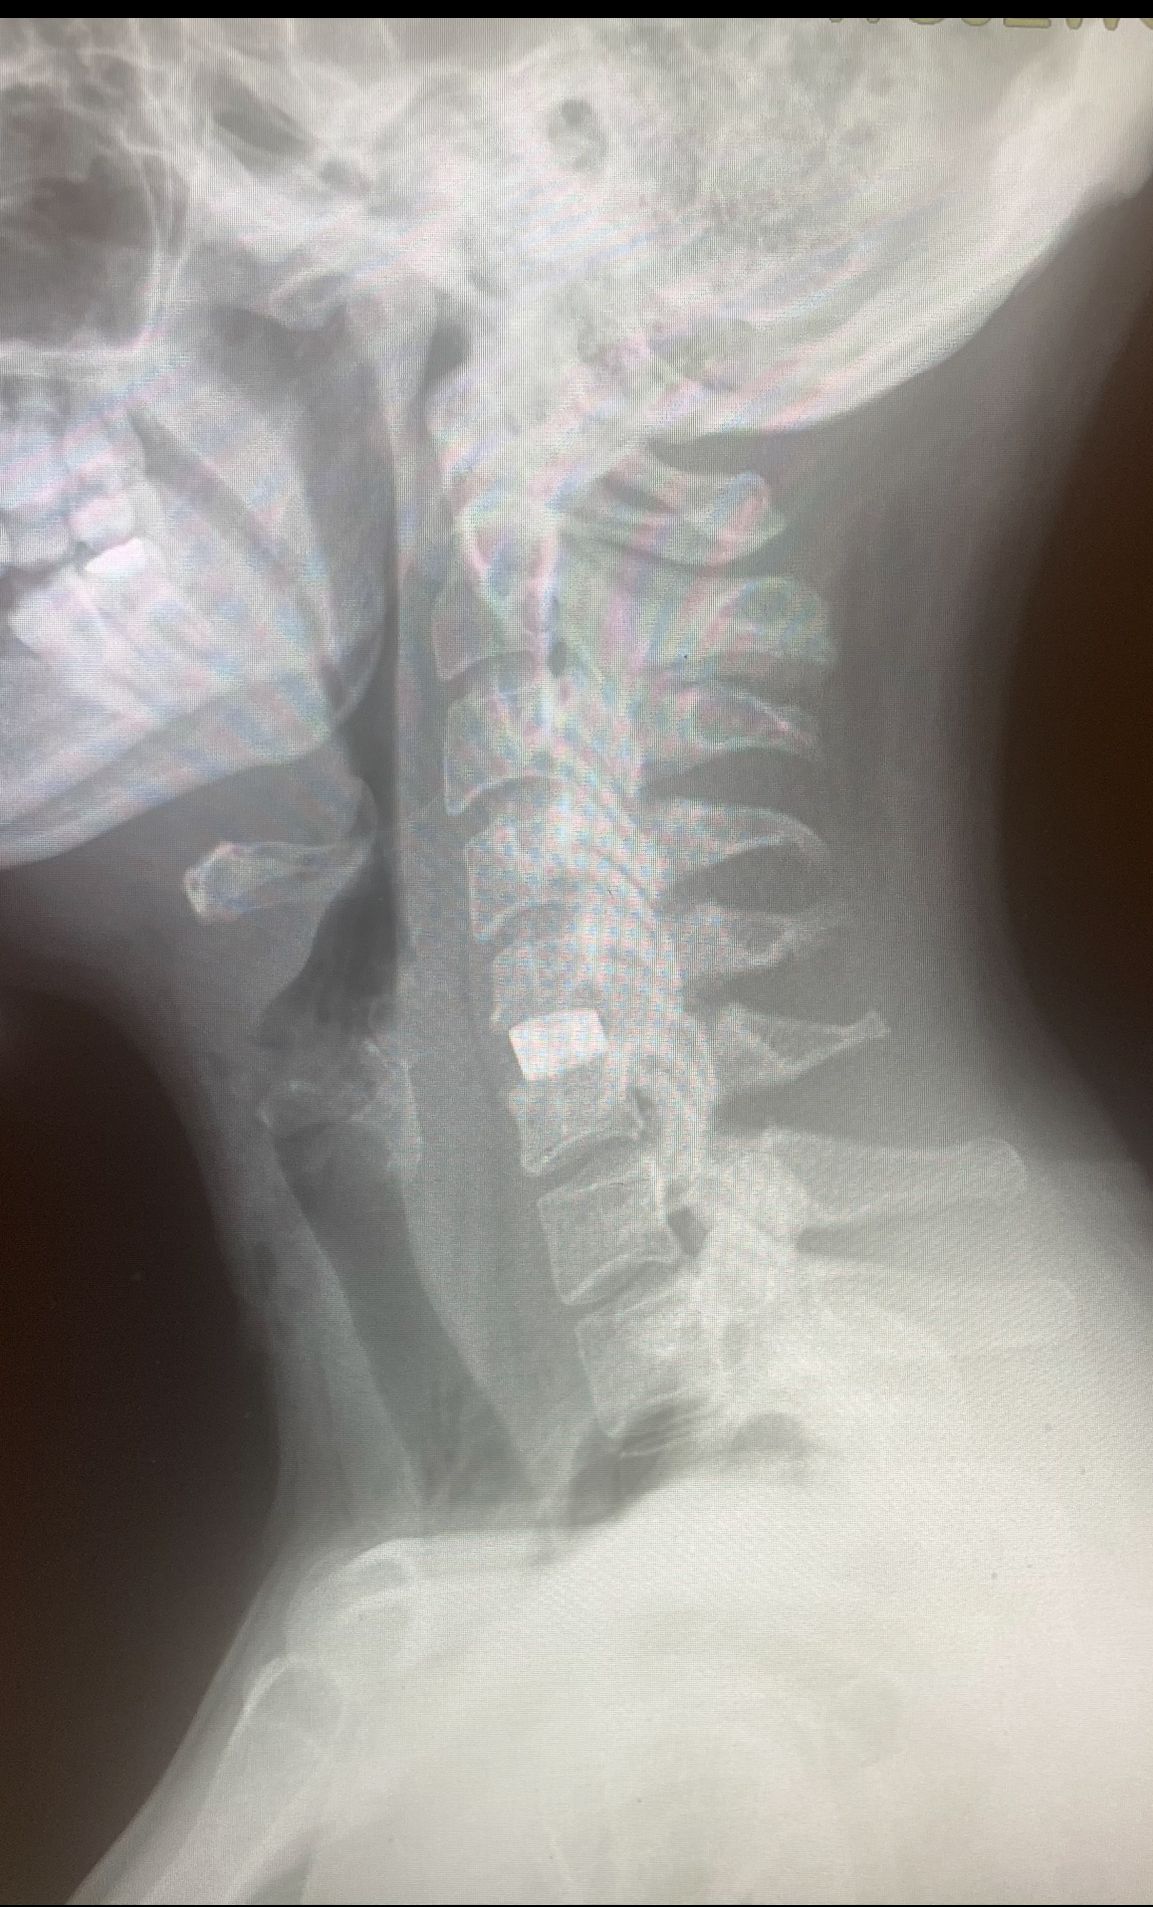

Starszy Asystent w Klinicznym Oddziale Neurochirurgicznym oraz Poradni Neurochirurgii Wojewódzkiego Szpitala Specjalistycznego im. św. Barbary nr 5 w Sosnowcu. Konsultant Kliniki Neurologii Szpitala Klinicznego nr 1 w Zabrzu. Absolwent Wydziału Lekarskiego Śląskiego Uniwersytetu Medycznego w Zabrzu. Staż podyplomowy odbył w latach 2010-2011 w Oddziale Neurochirurgii WSS nr 4 w Bytomiu. W 2018r. złożył egzamin specjalizacyjny po zakończeniu szkolenia w ramach rezydentury w WCM Opole. W 2019 roku uzyskał stopień doktora nauk medycznych. Specjalizuje się w kompleksowym leczeniu schorzeń kręgosłupa (dyskopatia, stenoza kanału kręgowego, kręgozmyk) oraz neuroonkologii. Szczególny zakres działań medycznych to nowoczesne, małoinwazyjne operacje kręgosłupa z wykorzystaniem technik endoskopowych (mikrodiscektomia - implanty rozprężalne), przezskórnych stabilizacji oraz mikrochirurgicznych dekompresji. Wykonuje procedury iniekcyjne; discoGEL, GelSTIX, kriolezje oraz blokady przeciwbólowe kręgosłupa odcinka szyjnego, lędźwiowo-krzyżowego a także stawów krzyżowo-biodrowych, które odgrywają istotną rolę w procesie diagnostyczno-leczniczym wielu zespołów bólowych. Na co dzień przeprowadza operacje w ramach kontraktu z NFZ. Członek Polskiego Towarzystwa Neurochirurgów oraz Polskiego Towarzystwa Chirurgii Kręgosłupa. Uczestnik wielu krajowych i zagranicznych kursów neurochirurgicznych, m.in. w Czechach, Słowacji, Niemczech, Włoszech, Danii, Austrii, Szwajcarii i USA. Autor licznych publikacji naukowych.

Zdjęcia i filmy